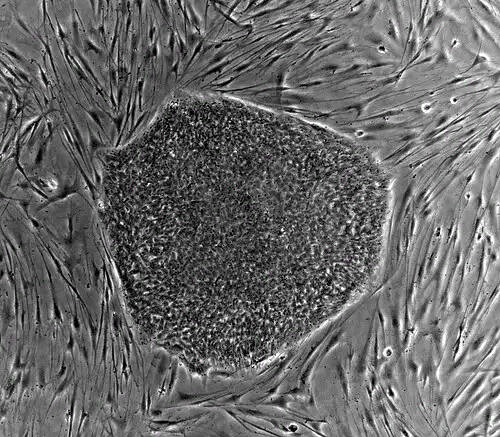

مهندسی بافت ( به انگلیسی: Tissue engineering ) به عنوان بخشی از دانش زیست فناوری، به طور عام به معنی توسعه و تغییر در زمینه رشد آزمایشگاهی مولکول ها و سلول ها در بافت یا عضو، برای جایگزینی یا ترمیم قسمت آسیب دیده بدن است. دانشمندان از سال ها قبل قادر به کشت سلول ها در خارج از بدن و محیط دو بعدی بودند، ولی فناوری رشد شبکه های پیچیده و سه بعدی سلولی برای جایگزینی بافت آسیب دیده اخیراً توسعه یافته است. بر اساس تعریف برای ساخت یک بافت به شیوه های مهندسی، نیاز به طراحی یک داربست با ساختار فیزیکی مناسب با امکان چسبندگی سلول ها به آن، مهاجرت سلولی، تکثیر سلولی و تمایز سلولی و در نهایت رشد و جایگزینی بافت جدید است که همگی این موارد باعث فراهم آوری محیط سه بعدی برای رشد و ارتباطات سلولی می شود.

مهندسی بافت استفاده از ترکیبی از سلول ها، روش های مهندسی مواد و عوامل بیوشیمیایی مناسب برای بهبود یا جایگزینی بافت های بیولوژیک است. مهندسی بافت شامل استفاده از داربست بافت برای ایجاد یک بافت جدید و زنده برای یک هدف پزشکی می باشد که با توجه به گستردگی و اهمیت این موضوع، می توان آن را به عنوان یک حوزه در نظر گرفت.

در حالیکه اغلب تعاریف مهندسی بافت طیف وسیعی از کاربردها را پوشش می دهد، در اصطلاح به معنی برنامه های کاربردی که بخشی یا کل بافت ( مثل استخوان، غضروف، رگ های خونی، مثانه، پوست، عضلات و غیره ) را ترمیم یا جایگزین می کند. اغلب بافتها نیاز به خواص مکانیکی و ساختاری برای عملکرد مناسب دارند. این اصطلاح نیز برای انجام توابع خاص بیوشیمیایی با استفاده از سلول ها در یک سیستم پشتیبانی مصنوعی ایجاد شده است ( مثلاً پانکراس مصنوعی یا کبدی مصنوعی ). اصطلاح بازسازی دارو اغلب به صورت مترادف با مهندسی بافت استفاده می شود، گرچه کسانی که در پزشکی احیا کننده فعالیت می کنند تأکید بیشتری بر استفاده از سلول های بنیادی برای تولید بافت ها دارند.

یک تعریف معمولی از مهندسی بافت، همان طور که توسط لانگر و وکانتی بیان شده است، "یک رشته بین رشته ای است که اصول مهندسی و علوم زیستی را در جهت توسعه جایگزین های بیولوژیکی که بازسازی، حفظ یا بهبود می یابند، اعمال می کند. همچنین مهندسی بافت به عنوان "درک اصول رشد بافت و استفاده از آن برای تولید بافت جایگزینی کاربردی برای استفاده بالینی" نیز تعریف شده است. شرح بیشتر می گوید که "فرضیه اصلی مهندسی بافت این است که کاربرد زیست شناسی طبیعی این سیستم، باعث موفقیت بیشتر در ایجاد استراتژی های درمانی می شود که با هدف جایگزینی، تعمیر، نگهداری یا بهبود عملکرد بافت" هستند. تحولات کلیدی درزمینه چند رشته ای مهندسی بافت مجموعه جدیدی از قطعات جایگزین بافت و استراتژی های پیاده سازی را به دست آورده است. پیشرفت های علمی در مواد بیولوژیکی، سلول های بنیادی، عوامل رشد و تمایز و محیط بیومیمتیک باعث ایجاد فرصت های منحصر به فرد برای ساخت بافت ها در آزمایشگاه از ترکیبات ماتریس خارج سلولی ( "داربست" )، سلول ها و مولکول های فعال بیولوژیکی شده است. در میان چالش های عمده در حال حاضر با مهندسی بافت، نیاز به عملکرد پیچیده تر است، همچنین ثبات عملکردی و بیومکانیک و عروق کشی در بافت های آزمایشگاهی که برای پیوند استفاده می شوند. موفقیت مداوم مهندسی بافت و توسعه نهایی واحدهای واقعی انسانی از همگرایی پیشرفت های مهندسی و تحقیقات اولیه در بافت، ماتریکس، عامل رشد، سلول های بنیادی و زیست شناسی توسعه، و همچنین مواد و علوم زیستی اصل شده است.